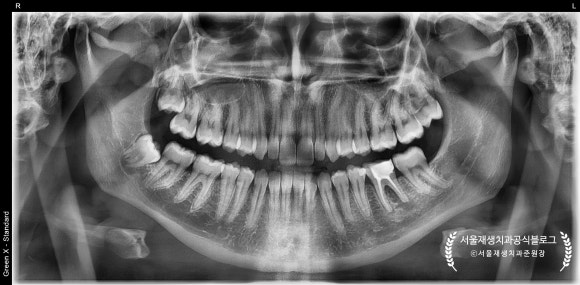

파노라마 엑스레이를 먼저 볼까요?

(정확한 진단에는 전체를 보는 눈이 필수입니다!)

왼쪽 아래 어금니 뿌리 주변이 심상치 않네요...

확대해보겠습니다.

파노라마를 확대해보니,

뿌리 쪽으로 까맣게 뼈가 녹아내린 모양이 관찰됩니다.

보다 정확한 진단 및 상황파악을 위해

치근단엑스레이를 추가로 촬영하였습니다.